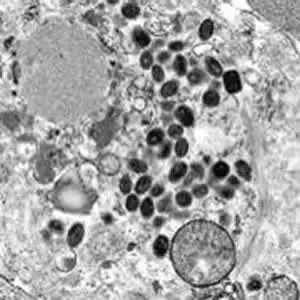

在人类与疾病漫长的博弈史上,从未有一种病原体像天花病毒那样,如此系统性地雕刻我们的基因、改写我们的文明、又最终被我们亲手埋葬。它在三千年的岁月里夺走了约五亿人的生命——这个数字超过了二十世纪所有战争死亡人数的总和。然而1980年,世界卫生组织宣布天花被彻底根除,这是人类医学史上唯一的胜利。这场胜利的代价是什么?那个被称为"魔鬼的砖块"的病毒,究竟如何在我们的身体内攻城略地?又是谁,在那个黑暗的年代,点燃了人类战胜瘟疫的第一束火光? ...

在人类与疾病漫长的博弈史上,从未有一种病原体像天花病毒那样,如此系统性地雕刻我们的基因、改写我们的文明、又最终被我们亲手埋葬。它在三千年的岁月里夺走了约五亿人的生命——这个数字超过了二十世纪所有战争死亡人数的总和。然而1980年,世界卫生组织宣布天花被彻底根除,这是人类医学史上唯一的胜利。这场胜利的代价是什么?那个被称为"魔鬼的砖块"的病毒,究竟如何在我们的身体内攻城略地?又是谁,在那个黑暗的年代,点燃了人类战胜瘟疫的第一束火光? ...